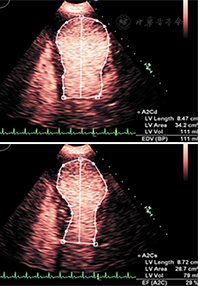

LVEF的准确测量对心血管疾病患者的治疗极为重要,对预测心肌梗死后及血运重建后充血性心力衰竭患者的不良事件具有重要价值。超声心动图是目前唯一能够床旁提供实时动态连续心脏解剖结构和功能动态评估的可视化医学影像技术方法,与其他影像技术相比,具有无电离辐射、容易获取、便携和成本相对较低的优势。已有研究发现常规的非增强超声心动图测量的LVEF与公认的金标准相比有显著差异,观察者间一致性低,因此严重影响了常规超声心动图心功能测量的实用性和可靠性。最近的一些研究表明,造影超声心动图测量左心室容积和LVEF与核素显像、MRI、CT有着良好的相关性,并且提高了观察者间的一致性及医师诊断信心[21,22,23](图3)。

在临床需要精确定量评估左心室容积和LVEF的情况时,如需要进行动态左心室功能评估(接受化疗、已知心脏衰竭患者在临床状态变化时的重新评估、心肌梗列后重构、心脏移植、瓣膜反流患者瓣膜置换术的时机确定、评价是否应当安置心内装置等),可以考虑使用造影检查[24]。